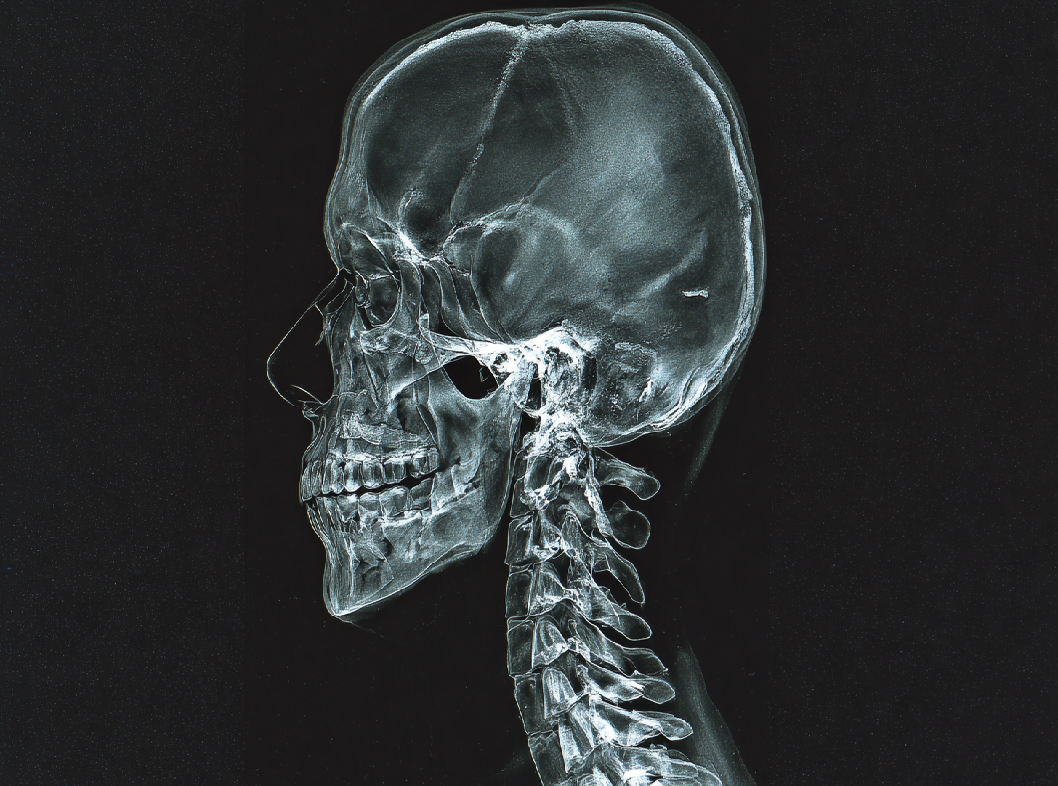

Диагностика синдрома черепно-шейного перекоса

Диагностика синдрома черепно-шейного перекоса включает в себя медицинский осмотр, анамнез (историю болезни), и в некоторых случаях проведение дополнительных обследований для исключения других возможных причин симптомов. Вот несколько шагов, которые могут быть включены в процесс диагностики:

- Обследование позвоночника. Рентгенография шейного отдела позвоночника может быть проведена для оценки структуры и выявления возможных аномалий.

- Исключение других причин. В некоторых случаях могут потребоваться дополнительные обследования, такие как компьютерная томография (КТ) или магнитно-резонансная томография (МРТ) для исключения других причин, таких как врожденные аномалии, опухоли или другие патологии.